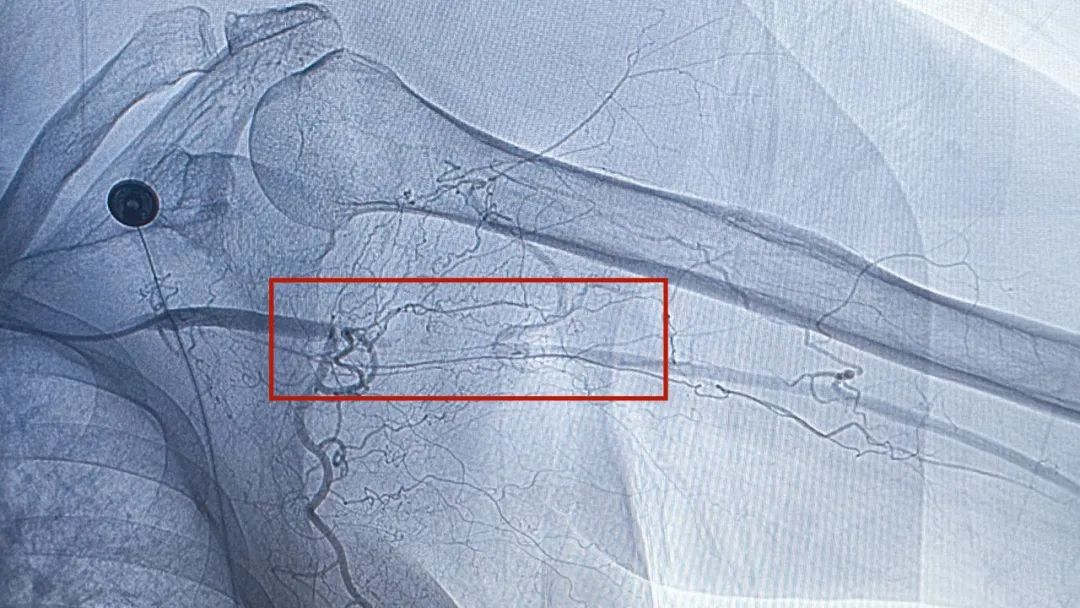

▲患者血管造影结果

提示左侧腋动脉急性血栓栓塞

当DSA揭示出左侧腋动脉4厘米的充盈缺损区时,主刀医生欧敏富副主任医师的手微微停顿——患者不排除存在腋动脉狭窄的情况,如按预定手术方式进行切开取栓,存在栓子取出不全甚至无法取出的可能,只能紧急改变治疗方案,予施动脉溶栓术+左上肢动脉血栓旋切取栓术。经过与家属进一步沟通血管造影情况并取得同意后,手术团队当即经MPA导管注入溶栓药物,血栓很快软化松动。